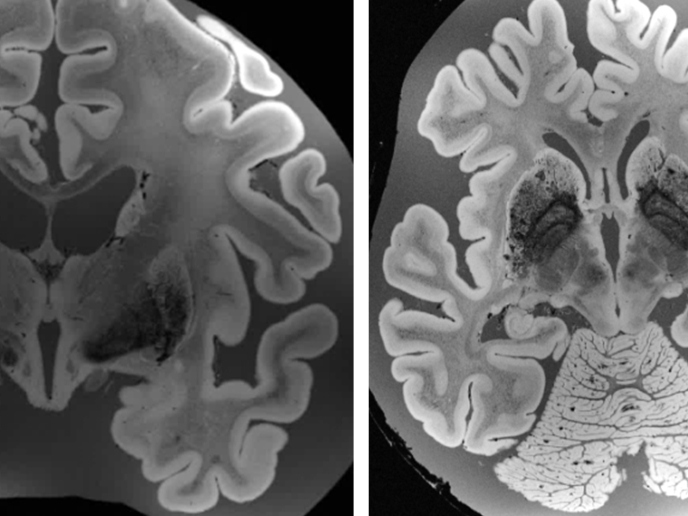

Nasza zdolność oceny głębi i postrzegania przedmiotów w trójwymiarze jest w znacznym stopniu związana z rozbieżnością dwuoczną. Ta rozbieżność jest kluczowa dla chwytania przedmiotów, sięgania po nie i posługiwania się nimi oraz takich umiejętności, jak prowadzenie samochodu, uprawianie sportu lub spożywanie pokarmów. Wcześniejsze badania dotyczące przetwarzania bodźców dwuocznych opierały się na ograniczonych danych pochodzących z niewielkiej liczby obszarów mózgu oraz wykorzystywały specjalnie przeszkolonych pacjentów i zwierzęta. Podczas finansowanego ze środków UE projektu "Neural substrates of depth perception: from surfaces to complex 3D forms" (COMPLEX3D) pracowano nad globalną analizą ról regionów grzbietowych i brzusznych mózgu w przetwarzaniu różnego rodzaju informacji w zakresie głębi. Analizowano też, czy sieci neuronalne odpowiedzialne za percepcję głębi wykazują plastyczność, gdy znaczenie behawioralne informacji na temat głębi jest modyfikowane poprzez szkolenia (uczenie się). Plastyczność to reorganizacja sieci neuronalnych w odpowiedzi na ponawiane szkolenia. Naukowcy korzystają z czynnościowego obrazowania metodą rezonansu magnetycznego (fMRI) i powtarzanej przezczaszkowej stymulacji magnetycznej (TMS), aby zidentyfikować obszary mózgu uczestniczące w postrzeganiu określonych kształtów i powierzchni. Naukowcy oceniali adekwatność zachowań uczestników badania, związanych z postrzeganiem prostych obiektów, oraz badali aktywność ich mózgów metodą fMRI podczas dokonywania oceny głębi. Bodźce przekazywały ogólne ("sygnał w szumie") lub precyzyjne informacje o głębi. Aby określić, jaki wpływ ma uczenie się na plastyczność, zespół zwiększył istotność behawioralną bodźców głębi poprzez odpowiednio opracowane szkolenia. Zastosowano powtarzaną przezczaszkową stymulację magnetyczną regionów mózgu uczestniczących w percepcji głębi podczas oceny głębi, aby wyjaśnić możliwe różnice w percepcji. Wyniki projektu COMPLEX3D potwierdziły znaczenie szkolenia w poprawie mechanizmów filtrowania szumów i percepcji głębi. Wyniki mają fundamentalne znaczenie dla zrozumienia szlaków wzrokowych uczestniczących w percepcji głębi. Ta wiedza może też znaleźć zastosowanie w rehabilitacji osób z urazami mózgu lub projektowaniu robotów.